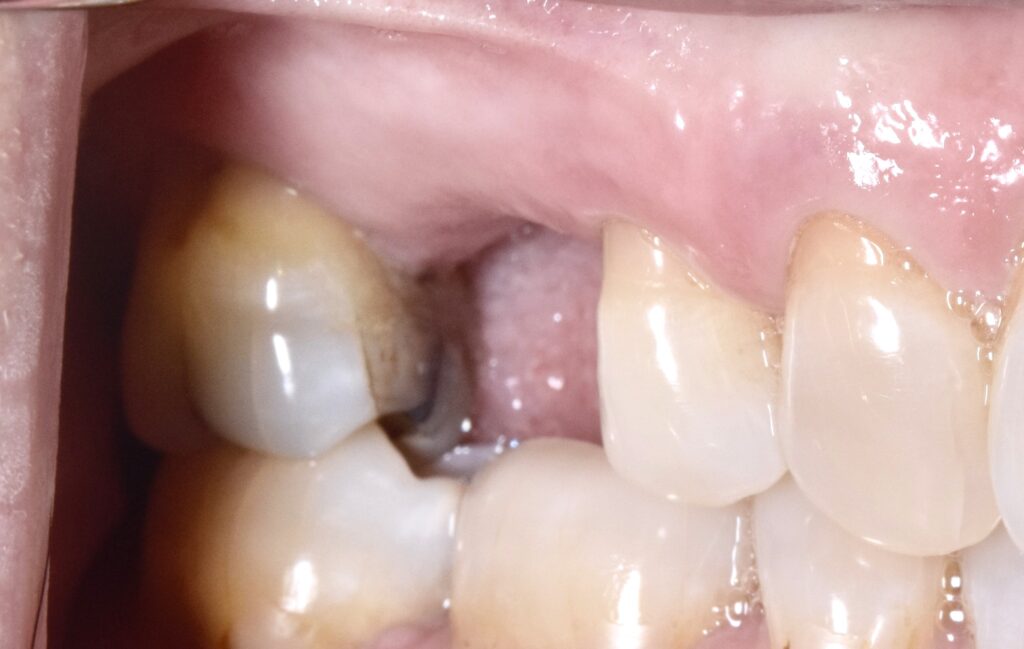

治療前

前歯部インプラント

治療後

折れてしまった歯を抜去し、周りの歯に調和したインプラント治療を行いました。